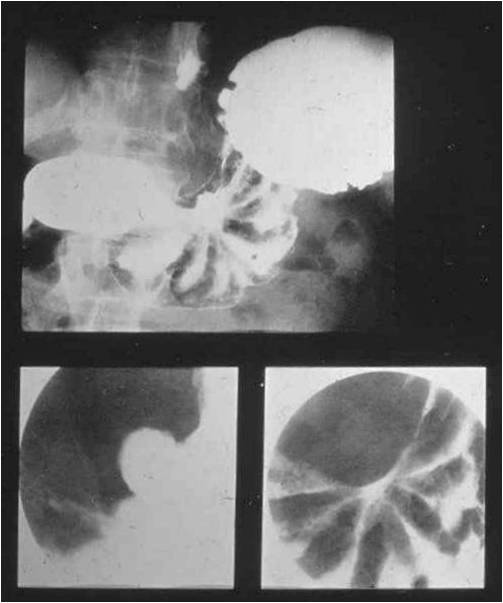

Image Image

Fig.8., 9.:Incarcerated hiatus hernia

A middle aged female with eight day history of abdominal pain was emergently admitted to the surgery department. The chest and abdominal radiographs showed no alteration, thus the patient was released home. Four days later she was readmitted to a different hospital where the upper GI series revealed an incarcerated hiatus hernia. Surgical exploration confirmed perforation of the ulcerated wall in the incarcerated gastric segment. Second review of the initial chest x-ray a found a right lower mediastinal soft tissue mass that had already been present at the time.

Upper GI series must be always performed in these patients!